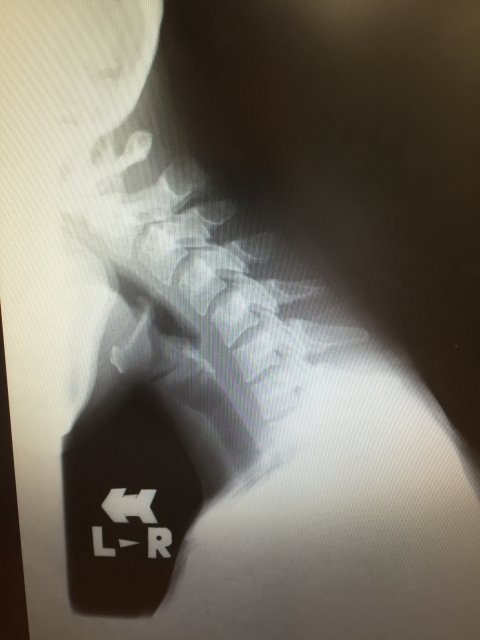

スマホを見る際に下を向く姿勢を続けると、本来あるべき首の骨のカーブが失われ、まっすぐになってしまいます。これが「ストレートネック」です。この状態では、首の筋肉が常に頭を支えるために「力み」続けている状態になり、筋肉が硬く血行不良を起こして痛みを発症します。